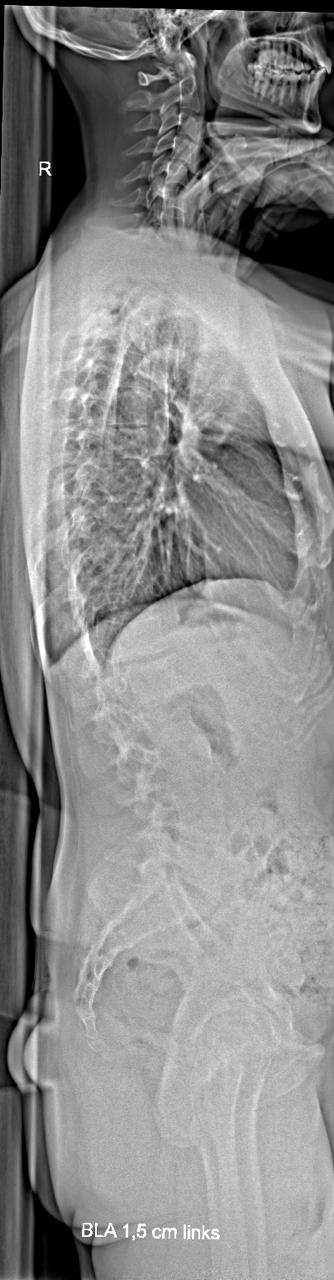

Das wurde gemacht, ich habe das Bild angehängt. Beim Orthopäden wurde dazu allerdings überhaupt nichts gesagt. Kannst du etwas auf dem Bild erkennen, das für mich relevant sein könnte? Ich habe da leider überhaupt keine Expertise.Eine Frage, die ich allen männlichen Usern mit Fehlstellungen stelle: Hast du evtl. auch einen Rundrücken (Hyperkyphose) oder ein Hohlkreuz (Hyperlordose)? Das sieht man in einem seitlich aufgenommenen Röntgenbild, das leider oft in der Diagnostik fehlt.

Dazu müsste man die entsprechenden Winkel kennen. Die sollten eigentlich auch in einer seitlichen Aufnahme grundsätzlich ermittelt werden.

Die natürliche BWS Kyphose bewegt sich in einem Bereich von 25°-40°. Die natürliche LWS Lordose in einem Bereich von 35°-55°.

Ferner könnte man vermuten, dass die HWS steilgestellt ist. Also eine Abschwächung der natürlichen HWS Lordose.

Also eine Hyperkyphose/Hyperlordose hast Du wohl nicht, es sieht eher so aus, als ob die natürliche BWS Kyphose etwas abgeschwächt ist.Kannst du etwas auf dem Bild erkennen, das für mich relevant sein könnte?